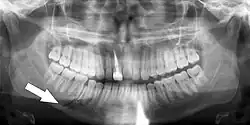

Root fracture

Simple mandible fracture

7) Root fracture Mobile or displaced crown segment

Tender tooth that may be bleeding from the gum

Tooth may be discoloured (red or grey)

Fracture line involving the root will be seen as well as the direction If displaced, reposition tooth and check the position with an x-ray

Flexible splint used to stabilise tooth for at least 4 weeks and then reassess tooth stability

Monitor healing for at least 1 year to assess the status of the pulp

Root canal treatment will be needed if pulp necrosis develops (this occurs in ~20% of root fractures)

4 weeks: splint removal, clinical and radiographic examination

6–8 weeks: clinical and radiographic examination

4 months: splint removal in cervical third fractures, clinical and radiographic examination

6 months: clinical and radiographic examination

1 year: clinical and radiographic examination

5 years: clinical and radiographic examination